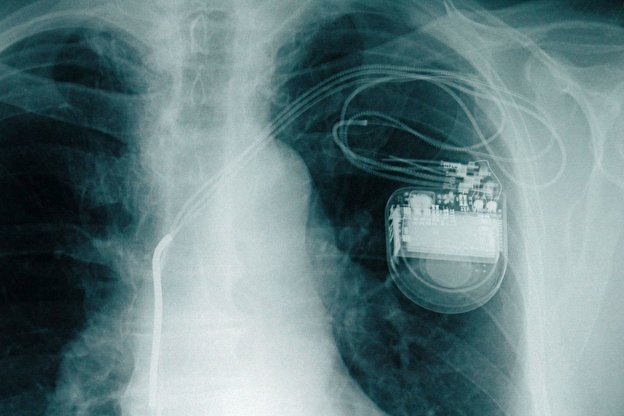

هل تؤثر الهواتف الذكية في منظم ضربات القلب؟

هناك اعتقاد شائع بأن الأجهزة الإلكترونية كالهواتف الذكية لها تأثير سلبي في وظيفة منظم ضربات القلب.. فما مدى صحة هذا الاعتقاد؟

للإجابة عن هذا السؤال؛ أوضح طبيب القلب الألماني الدكتور فلوريان بلاشكه، أن الأجهزة الإلكترونية لا تشوش على وظيفة منظم ضربات القلب أو مُزيل الرجفان إلا في حالات نادرة للغاية.

وأضاف أنه لتجنب أي تأثير سلبي ينصح بوجود مسافة أمان بين منظم ضربات القلب أو مُزيل الرجفان والأجهزة الإلكترونية، وتبلغ مسافة الأمان 10 سم مع محطات الشحن بتقنية «الحث الكهربائي»، و15 سم مع الهاتف الذكي، و25 سم مع الموقد العامل بتقنية «الحث الكهربائي».